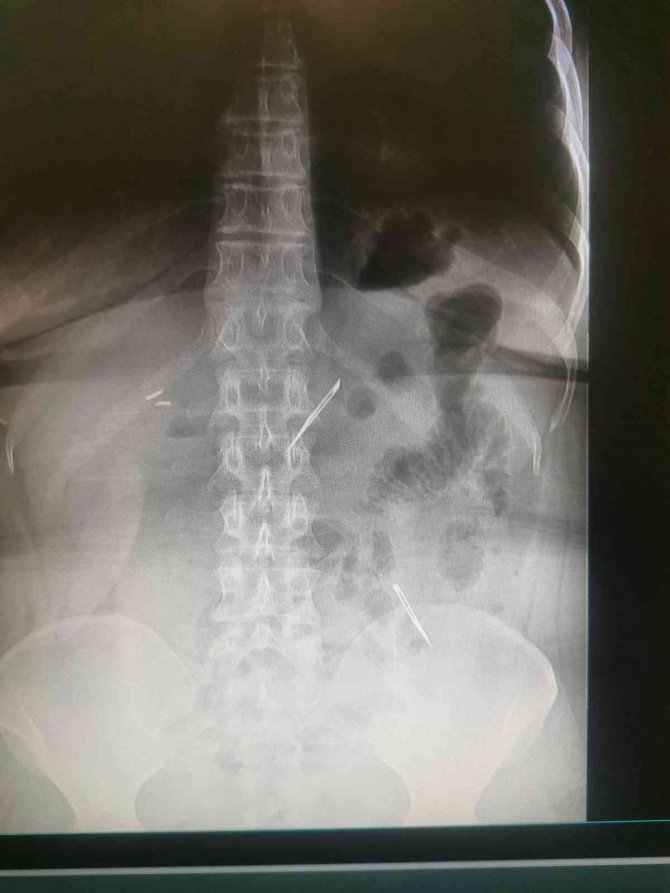

Sağlık Bilimleri Üniversitesi Ankara Atatürk Sanatoryum Eğitim ve Araştırma Hastanesi'ne mide ve karın bölgesinde aşırı ağrı şikayeti ile müracaat eden 46 yaşındaki D.E.'nin yapılan tahlil, tetkik ve çeşitli görüntülemelerden sonra bağırsak kısmında 2 adet neşter olduğu tespit edildi. Genel cerrahi kliniği tarafından zorlu bir ameliyat sonrasında neşterler kadının vücudundan çıkarıldı. 46 yaşındaki D.E. neşterleri nasıl yuttuğunu bilmediğini tahminen ekmek ile birlikte yutabilmiş olabileceğini ifade etti. Ameliyatı gerçekleştiren Sağlık Bilimleri Üniversitesi Ankara Atatürk Sanatoryum Eğitim ve Araştırma Hastanesi Genel Cerrahi Kliniği Eğitim ve İdari sorumlusu Prof. Dr. Hakan Buluş ise hastanın yoğun şikayetleri üzerine çektikleri röntgen sonrasında 2 adet neşteri görünce şaşkına uğradıklarını söyledi.

Hastanın şikayetlerinin artması üzerine gerçekleştirilen tetkiklerde 46 yaşındaki kadının karın bölgesinde 2 adet yabancı cisim olduğunu tespit ettiklerini, detaylı inceleme sonucunda bu cisimlerin neşter olduğunu fark ettiklerini belirten Prof. Dr. Buluş, "Yaklaşık 10 gün önce kliniğimize karın ağrısı ve bulantı şikayetleri ile başvurdu. Bizim yaptığımız fiziki muayene ve tetkiklerinde hastanın direkt karın grafisinde 2 adet yabancı cisim olduğunu tespit ettik. Aslında yabancı cisim bizim güncel grafiğimizde sık karşılaştığımız bir durum değil, fakat nadir de olsa görebildiğimiz bir patoloji. Biz de bunun üzerine ayrıntılı değerlendirmeler ve tetkikler yaptık. Sonrasında 2 adet yabancı cismin bistüri (neşter) ile uyumlu olduğunu gördük. Bunun üzerine hastanın şikayetlerinin de artması üzerine, ameliyat kararı verdik. Yaptığımız ameliyatta ince bağırsağın yaklaşık 180'inci santimetresinde bu yabancı cisimlerin olduğunu tespit ettik. Bunun üzerine ameliyatla bunları çıkarttık. Hastamızın sağlık durumu şuan gayet iyi. Ameliyattan sonraki üçüncü günü. Şuan bir problemi yok, inşallah birkaç gün içerisinde şifa ile taburcu etmeyi düşünüyoruz" şeklinde konuştu.

Çıkardıkları cismin, neşterin normalde ameliyatlarda kullanılan bir malzeme olduğunu söyleyen Prof. Dr. Buluş, "Çıkardığımız yabancı cisimler bizim ameliyatlarda sıkça kullandığımız 11 numara dediğimiz bir bistüri tipi. Ebatları da yaklaşık 4 santime yarım santim ebatlarında. Ucunun sivri olması nedeniyle ince bağırsak mukozasına saplanarak enflamasyon ve bir karın ağrısı yapması, sonrasında da ağrı şikayetlerinin artmasına neden olmasından dolayı ameliyat kararı verdik" diye konuştu.